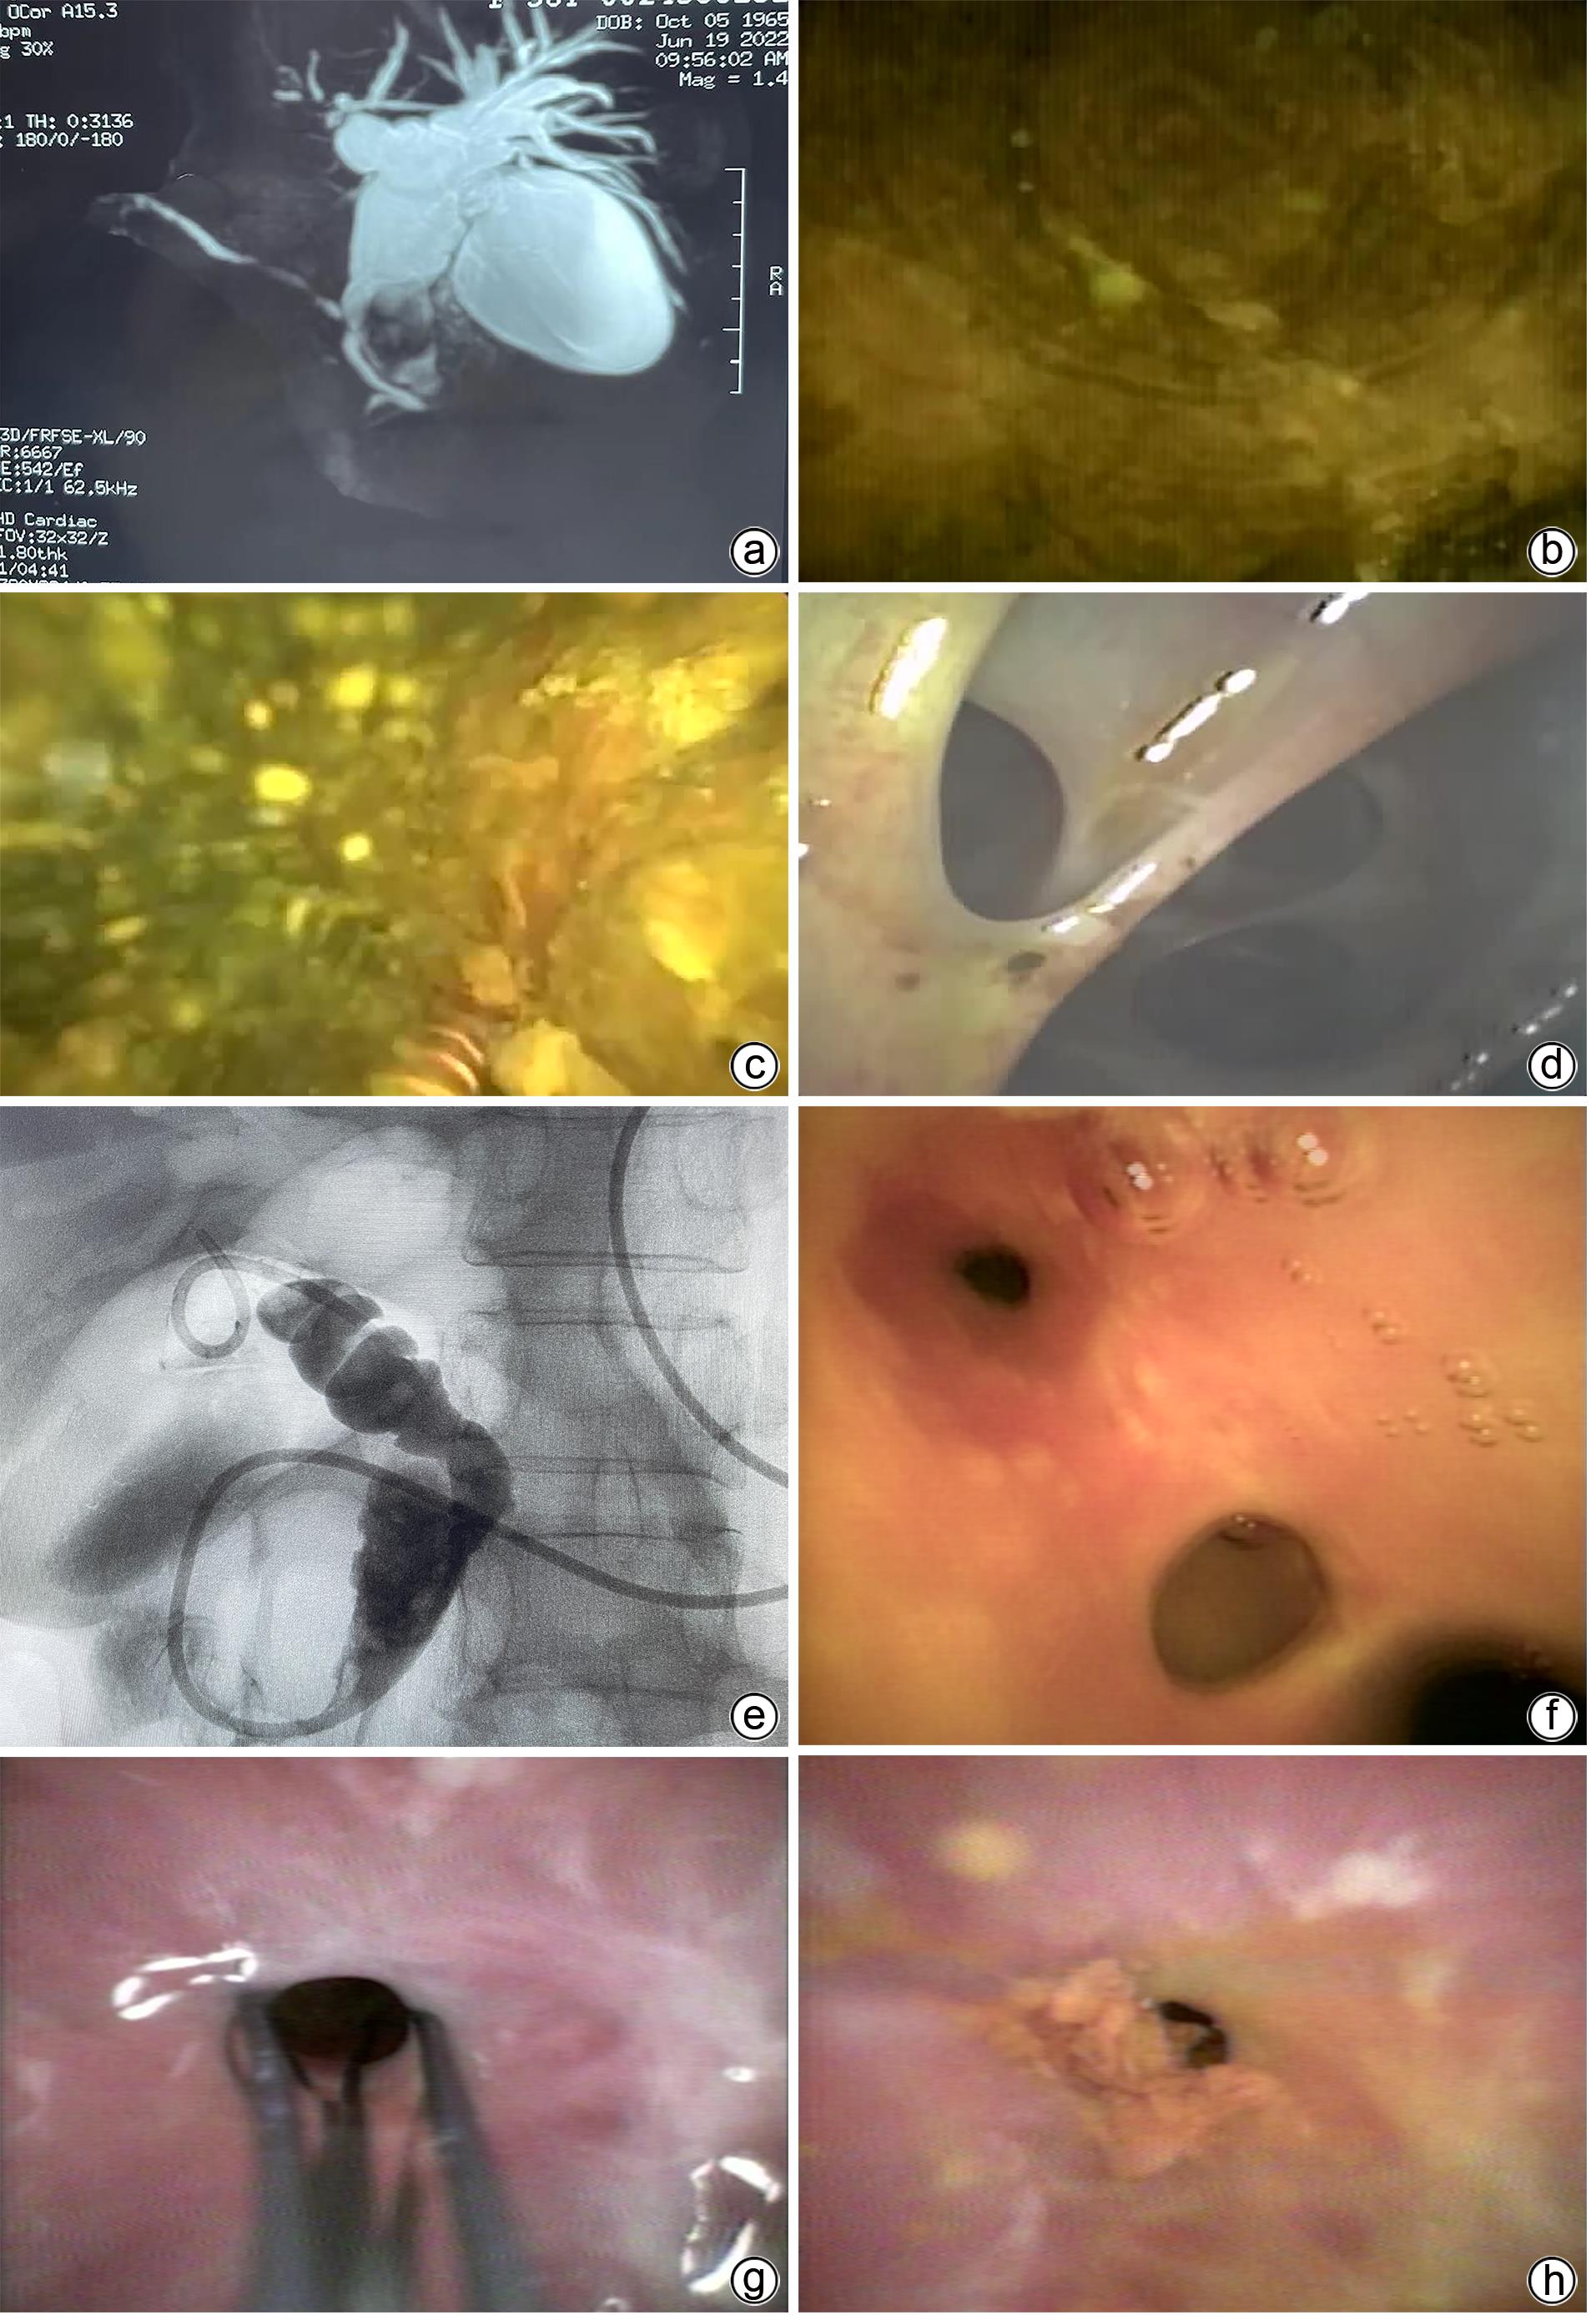

Objective  To investigate the safety and efficacy of endoscopic retrograde cholangiopancreatography (ERCP) combined with electrohydraulic lithotripsy under the direct view of eyeMax biliary-pancreatic imaging system in the treatment of difficult choledocholithiasis.  Methods  A retrospective analysis was performed for the clinical data of 12 patients with difficult choledocholithiasis who underwent ERCP and electrohydraulic lithotripsy under the direct view of eyeMax biliary-pancreatic imaging system in Department of Gastroenterology, Jilin People’s Hospital, from May to November 2022. The clinical effect of lithotripsy and lithotomy was observed, and postoperative complications and time of surgical operation were assessed.  Results  Among the 12 patients, 11 (91.67%) were successfully treated by electrohydraulic lithotripsy under direct view, 9 (75.00%) achieved first-attempt success in lithotripsy, and 11 (91.67%) had complete removal of calculi; 1 patient was found to have stenosis of the bile ducts caused by multiple biliary tract surgeries, and grade Ⅱ intrahepatic bile duct stones above the sites of stenosis were removed under direct view, but there were still residues of grade Ⅲ intrahepatic bile duct stones, which led to the fact that complete calculus removal was not achieved. The mean time of ERCP operation was 91.3±26.2 minutes, including a time of 41.8±22.2 minutes for energy lithotripsy. There were 2 cases of postoperative biliary tract infection which were improved after anti-infective therapy, 2 cases of hyperamylasemia which were not given special treatment, and 3 cases of mild pancreatitis which were improved after symptomatic medication, and there were no complications such as bleeding and perforation.  Conclusion  ERCP combined with electrohydraulic lithotripsy under the direct view of eyeMax biliary-pancreatic imaging system is safe, effective, and feasible in the treatment of difficult choledocholithiasis.